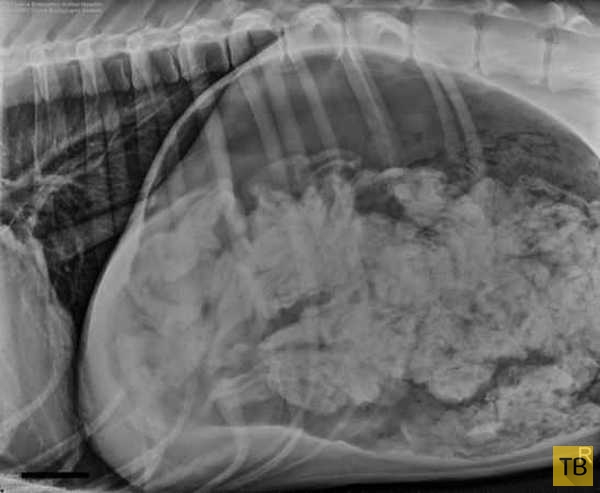

После того, как хозяева четвероногого пациента ответили на все вопросы ветеринаров и заполнили документы, доктор Эшли Маги (Ashley Magee) отвела собаку на рентгенологическое исследование. Полученный снимок насторожил специалистов - в желудке дога находилось большое количество инородных предметов.

“Инородные предметы скопились в желудке и их было настолько много, что они явно не могли быть переварены, - объясняет сотрудница больницы Шона Хач (Shawna Harch). - Это означало, что собаке придется делать операцию”.

Эта история стала достоянием общественности после того, как врачи предоставили рентген для участия в конкурсе журнала для ветеринаров на самые необычные находки, обнаруженные внутри животных. Несмотря на поразительное количество съеденных собакой носков, ветеринары из Портленда заняли третье место, отмечает Los Angeles Times.

После того, как хозяева четвероногого пациента ответили на все вопросы ветеринаров и заполнили документы, доктор Эшли Маги (Ashley Magee) отвела собаку на рентгенологическое исследование. Полученный снимок насторожил специалистов - в желудке дога находилось большое количество инородных предметов.

“Инородные предметы скопились в желудке и их было настолько много, что они явно не могли быть переварены, - объясняет сотрудница больницы Шона Хач (Shawna Harch). - Это означало, что собаке придется делать операцию”.

Эта история стала достоянием общественности после того, как врачи предоставили рентген для участия в конкурсе журнала для ветеринаров на самые необычные находки, обнаруженные внутри животных. Несмотря на поразительное количество съеденных собакой носков, ветеринары из Портленда заняли третье место, отмечает Los Angeles Times.